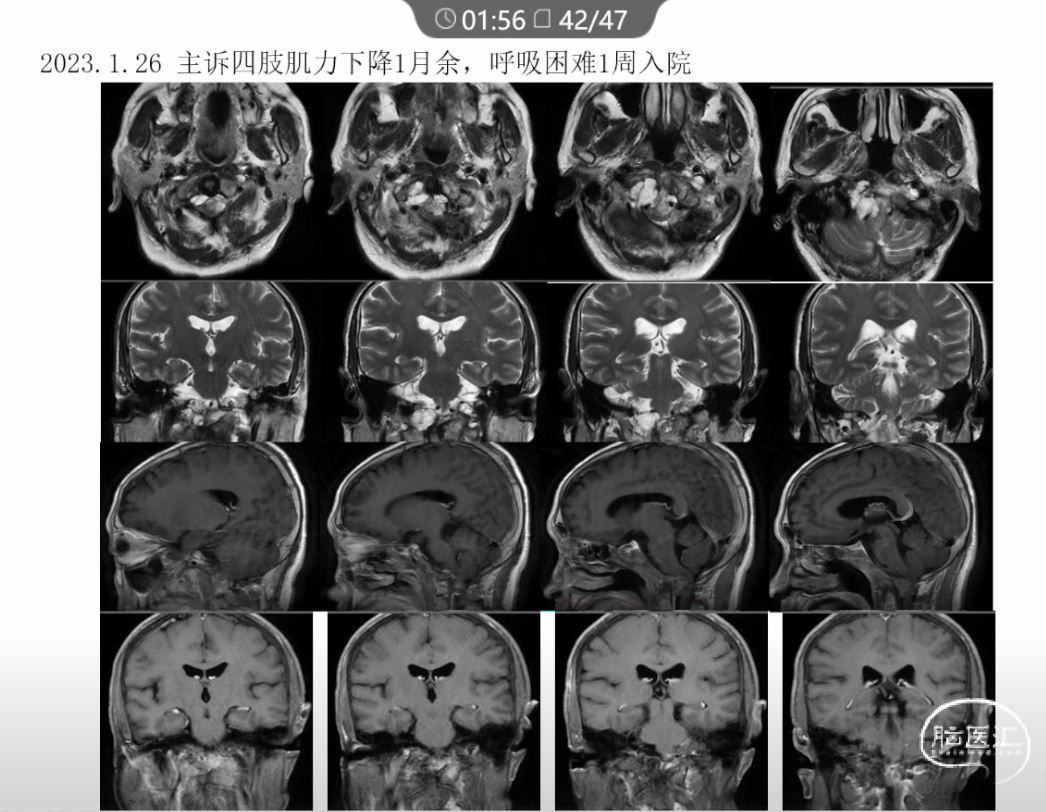

本文主要内容为:脊索瘤临床特点、治疗选择,以及多个手术病例。